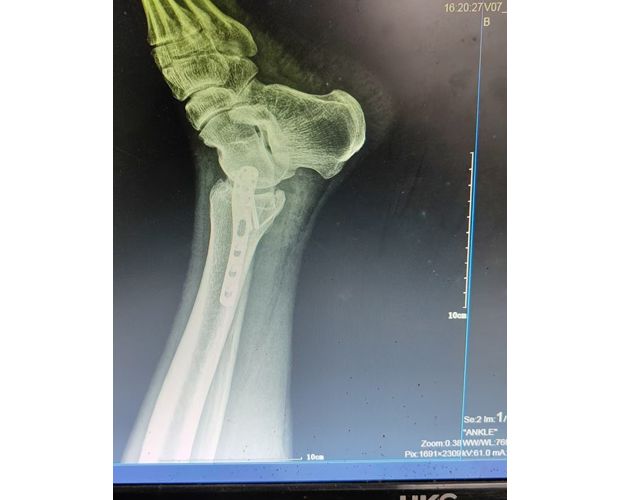

2月4日,何店鎮(zhèn)中心衛(wèi)生院接診一名左踝關(guān)節(jié)外傷患者,經(jīng)影像檢查,確診為左脛、腓骨下段骨折。外科醫(yī)生姜穩(wěn)迅速完成術(shù)前檢查及病情評估,并與患者及家屬深入溝通治療方案。在患者強烈要求于本院進行手術(shù)的情況下,為最大限度保障手術(shù)質(zhì)量與安全,該院特邀請醫(yī)共體牽頭單位——曾都區(qū)人民醫(yī)院脊柱創(chuàng)傷外科專家團隊前來指導(dǎo)。

本次幫扶由曾都區(qū)人民醫(yī)院脊柱創(chuàng)傷神經(jīng)外科主任徐三軍帶隊,專家團隊抵達后立即完成手術(shù)風險評估及術(shù)前準備。手術(shù)過程中,徐三軍主任嚴格規(guī)范完成各項手術(shù)操作,并同步結(jié)合手術(shù)步驟,為該院外科醫(yī)師詳細講解骨折手術(shù)的關(guān)鍵要點、操作技巧、術(shù)中注意事項及術(shù)后康復(fù)要領(lǐng)。通過“手把手”的實戰(zhàn)帶教,專家將豐富的手術(shù)經(jīng)驗與規(guī)范的診療思路傾囊相授,讓該院醫(yī)護人員在實操中學(xué)習(xí),在過程中成長。